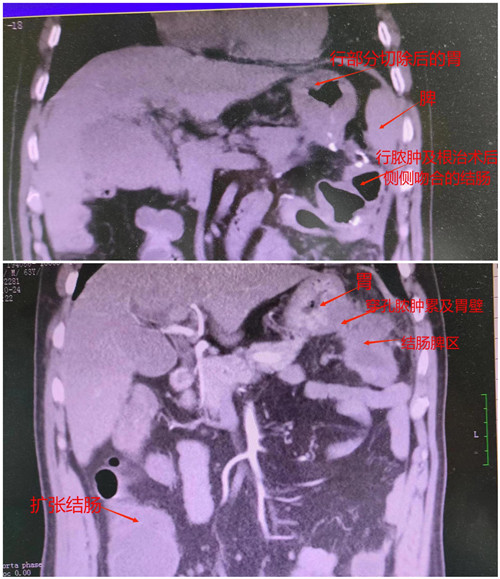

近期捷克论坛 普外三病区收治了一个63岁的结肠癌致梗阻并穿孔的患者刘先生,刘先生癌肿位置处于脾区侵犯胃壁,穿孔处已形成脓肿。入院时已处于重度感染和中度贫血状态,既往有结核病史,CT提示肺气肿。

以刘先生脾区癌肿梗阻和穿孔的病情,本应立即行急诊手术造口,待条件成熟再行造口回纳术。但他不愿接受二期手术,坚决拒绝做造口,而且重度感染加上贫血让其暂时无法耐受手术。普外三病区在谭浩翔主任的带领下,积极为其做抗感染治疗准备手术,同时另想它法。

术中医生们严阵以待,因刘先生的癌肿在脾区,脾质脆,术中稍有不慎即会伤及脾,若脾受伤极难修补,因而脾损伤多行脾切除。最后在谭浩翔主任的精细操作下,顺利完成腹腔镜下左半结肠癌根治+胃部分切除+肠粘连松解术。术中出血量小,脾脏无损伤。